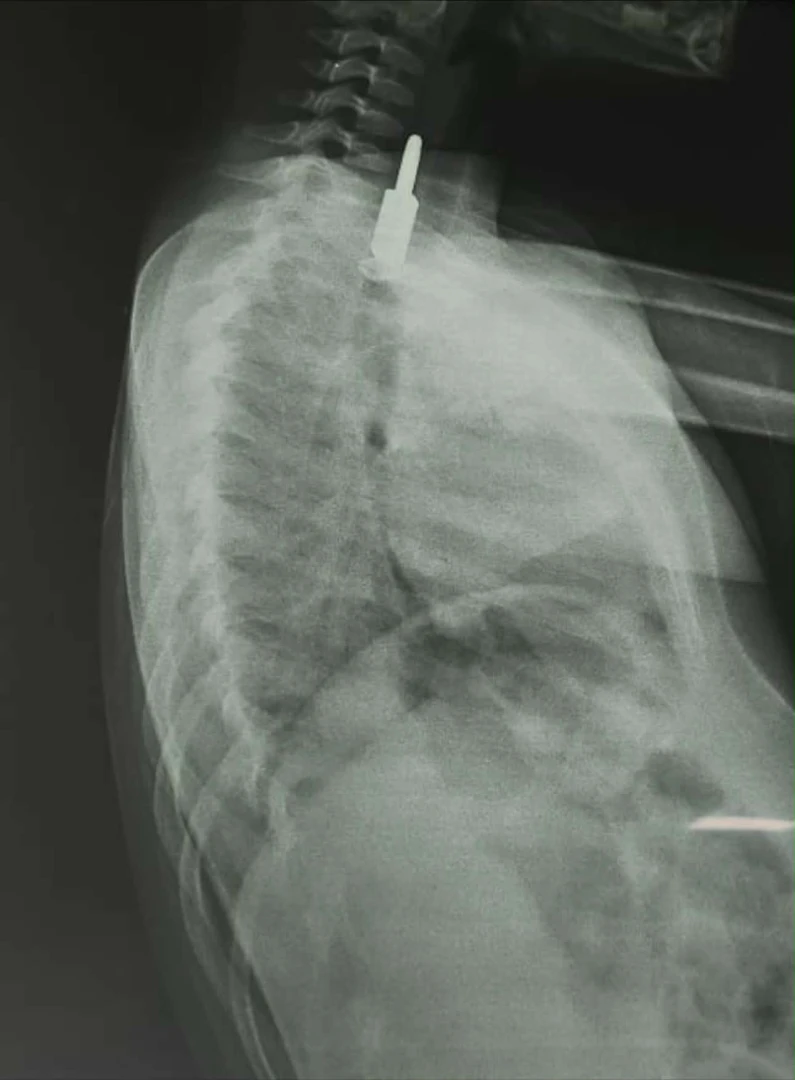

حبوب المخدرات المضبوطة والقفل داخل جسم الطفل بفحص الأشعة

حبوب المخدرات المضبوطة والقفل داخل جسم الطفل بفحص الأشعة

أما في النجف، فقد ذكرت دائرة صحة المحافظة في بيان ورد لوكالة شفق نيوز، أن مستشفى الزهراء التعليمي/ قسم جراحة الأطفال استقبل حالة طارئة لطفل يبلغ من العمر أربع سنوات قام بابتلاع جسم غريب.

وبعد إجراء فحص بالأشعة السينية للطفل تبين وجود "قفل" داخل جسمه، وعلى إثر ذلك، بحسب دائرة الصحة، تم التنسيق مع مدينة الصدر الطبية / قسم جراحة القلب والأوعية الدموية لاستخراج "القفل"، وتم ذلك بنجاح عن طريق الناظور، والطفل الآن بحالة صحية جيدة.